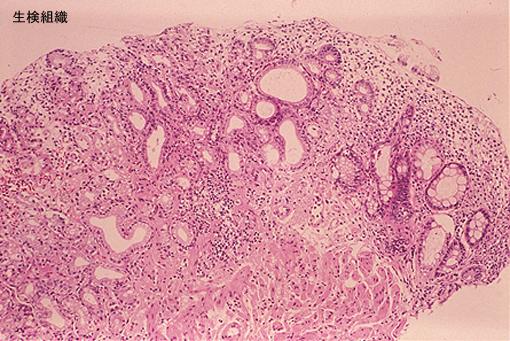

疾病(病理主体)的分类肿瘤样病变/异位粘膜

部位(按器官分)大肠/直肠

检查方法病理切片(微观)

肿瘤最大直径10~14